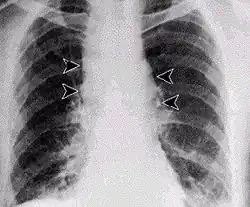

Plicní anthrax

Plicní anthrax se vyznačuje vysokou úmrtností, bez lékařského zákroku končí téměř vždy smrtí. Aby byl lékařský zásah úspěšný, vyžaduje včasnou diagnózu. Příznaky se podobají nejdříve silné chřipce, pak silnému zápalu plic. Léčba probíhá za pomoci silných dávek antibiotik. Letální dávku představuje 10–20 tisíc spor, inkubační doba se pohybuje mezi jedním a několika dny. V anglicky mluvících zemích se tato nemoc může někdy nazývat Wool-sorters' disease (nemoc třídičů vlny), český ekvivalent je „hadrářská nemoc“.